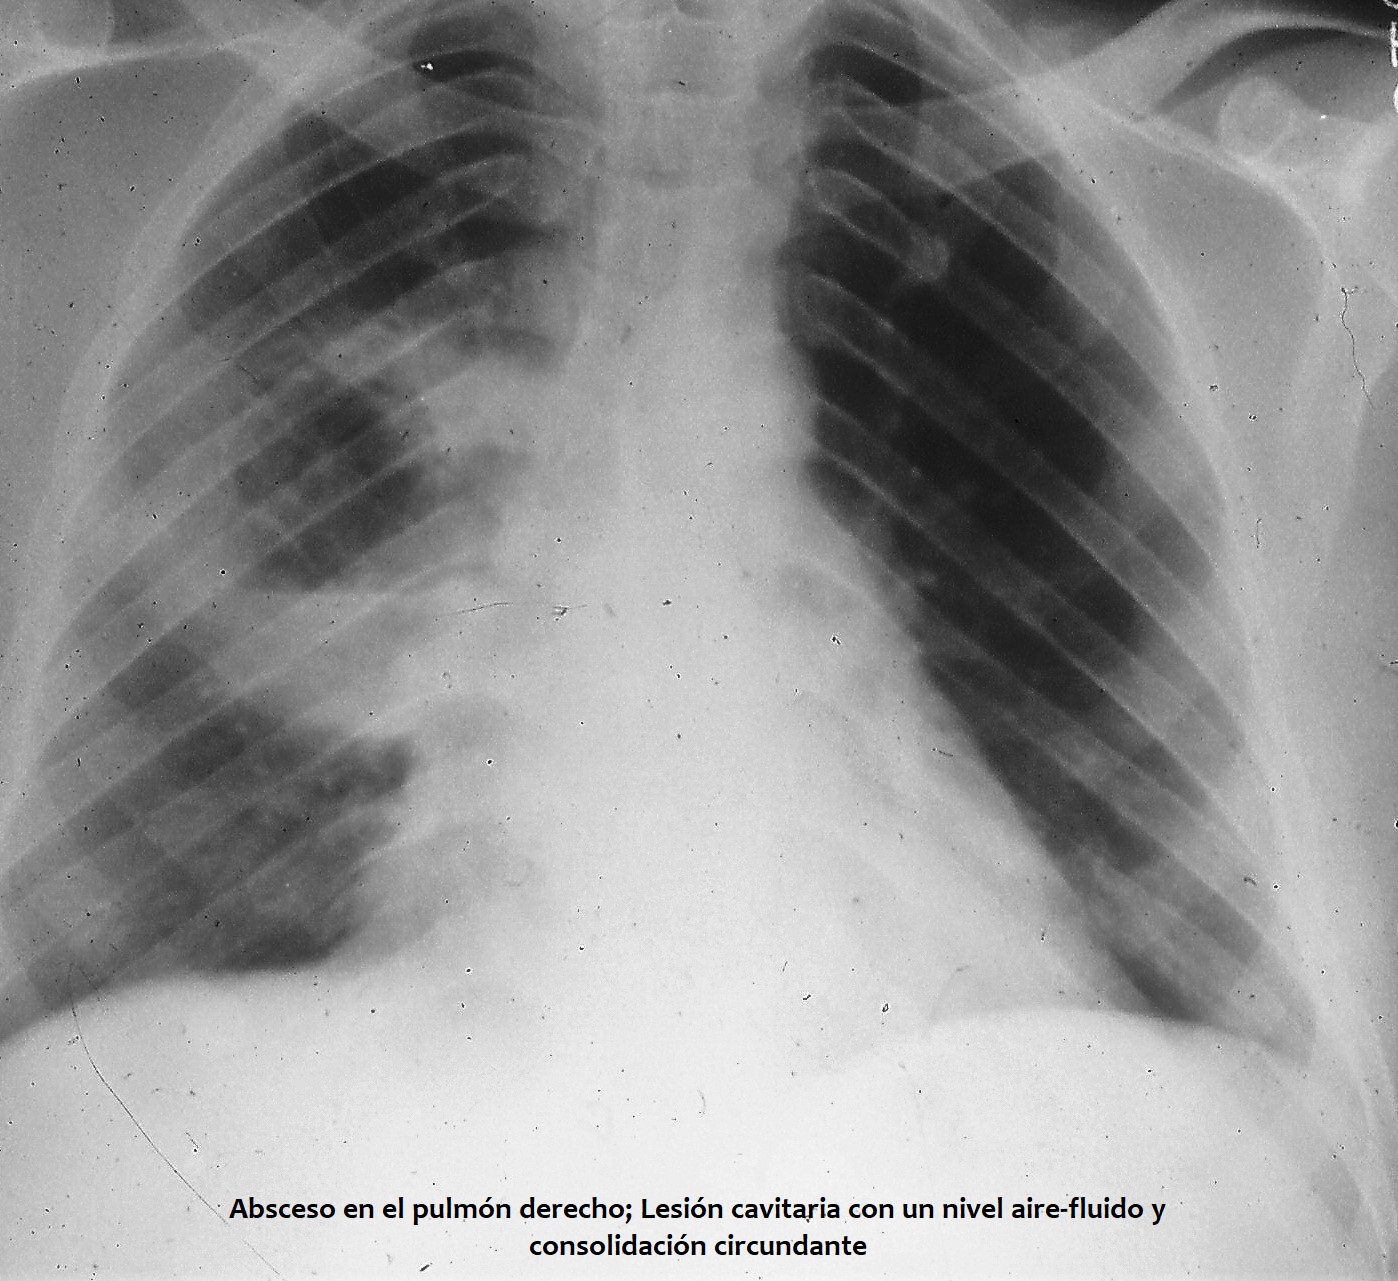

- El absceso pulmonar es una acumulación circunscrita de pus en el pulmón que da lugar a la formación de una cavidad, normalmente con un nivel hidroaéreo visible en la radiografía de tórax.

- El diagnóstico se basa en hallazgos radiológicos que revelan cavitación con nivel hidroaéreo. Por lo general, documentar la infección por anaerobios resulta difícil.